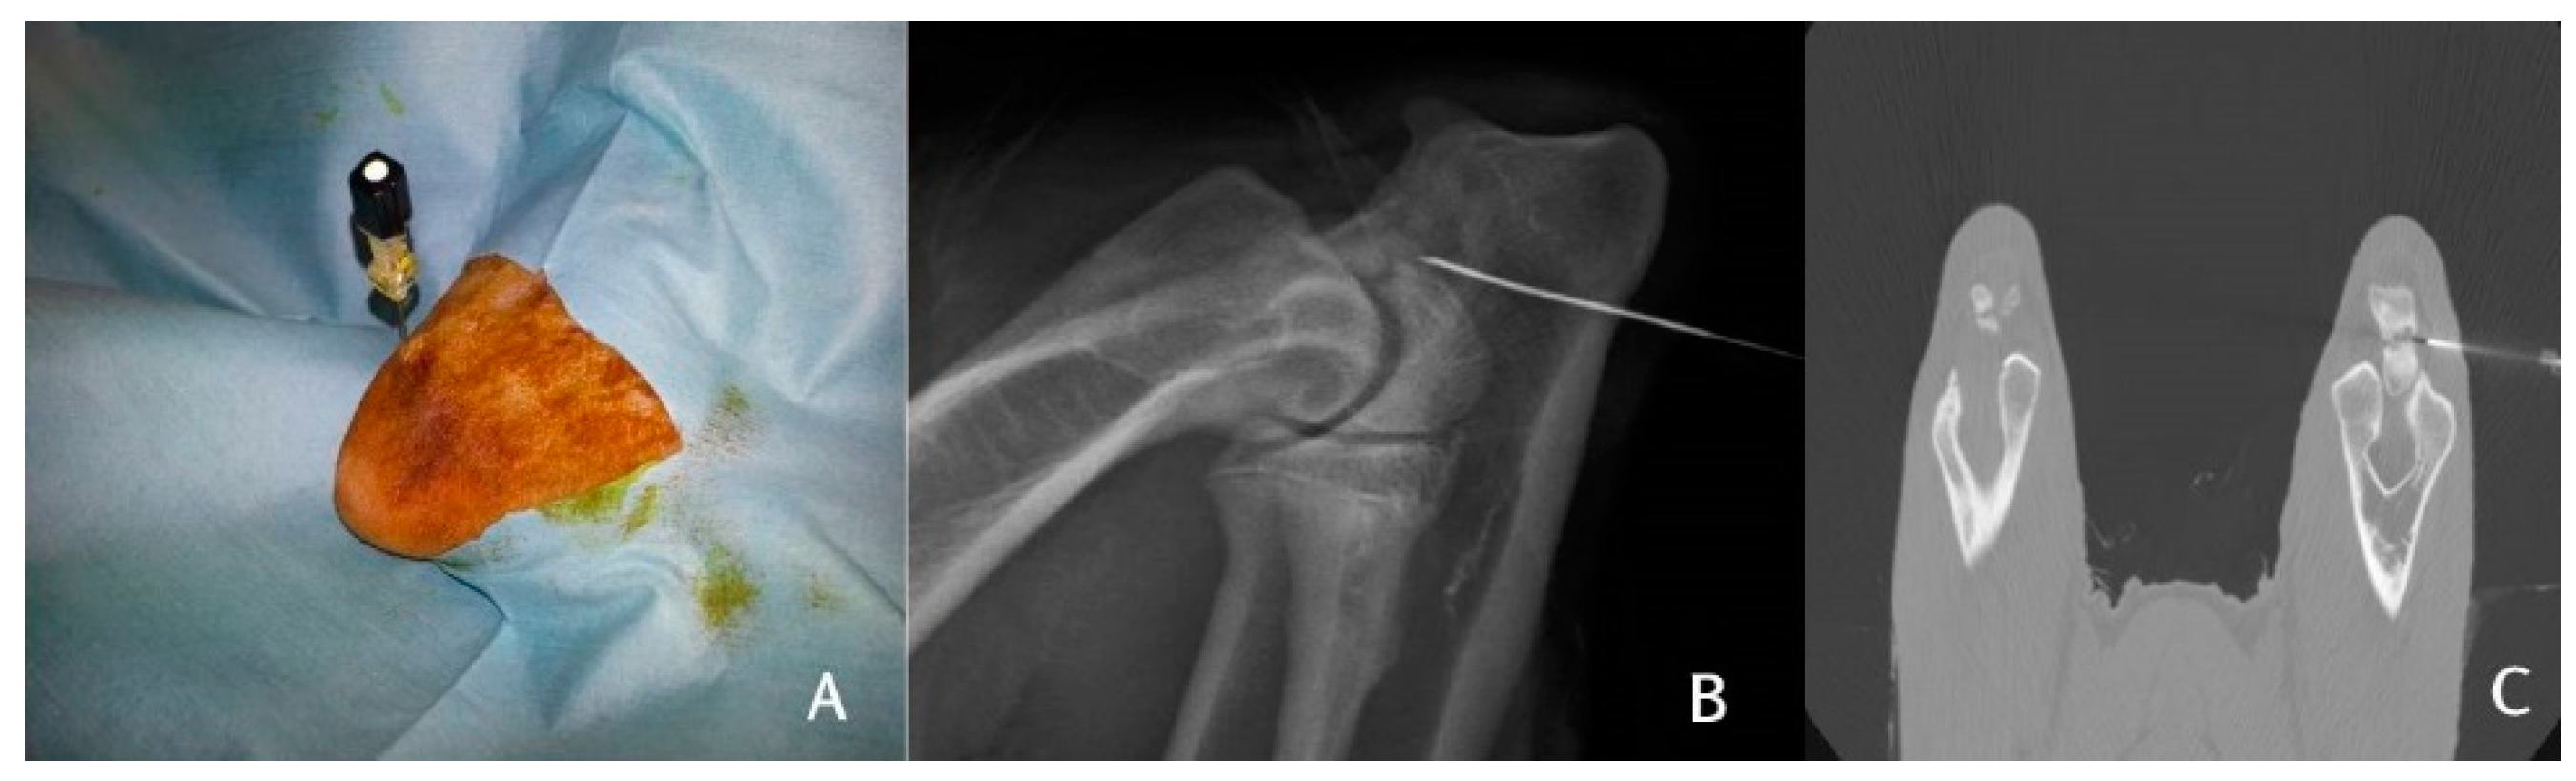

2.4. Bone Marrow Harvesting

2.5. Bone Marrow Processing and BMMC Isolation

2.6. BMMC Injection

3.1. X-ray Results

3.2. CT Results